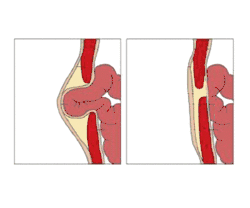

Normally, the abdominal muscles converge and fuse at the umbilicus during the formation stage, however, in some cases, there remains a gap where the muscles do not close and through this gap the inner intestines come up and bulge under the skin, giving rise to an umbilical hernia. The bulge and its contents can easily be pushed back and reduced into the abdominal cavity.

If hernias are symptomatic and disturb daily activity or have had episodes of threatening incarceration, preventive surgical treatment can be considered. The surgery is performed under anaesthesia, while the surgeon identifies the edges of the defect and bring them together permanently using either suture or mesh.[14] Small umbilical hernias are often successfully repaired with suture, while larger hernias may require a suitable mesh,[15] although some surgeons advocate mesh treatment for most hernias. The most common complications for both techniques are superficial wound infections and recurrence of the hernia[16] and some people experience pain at the surgical site.[17]